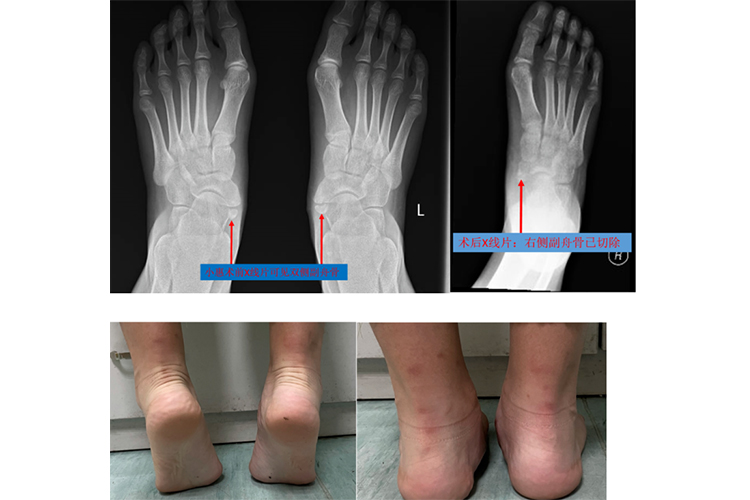

先天性副舟骨:常为双侧发病,足纵弓塌陷,舟骨结节突出,局部肿胀压痛,足抗阻力内翻活动时疼痛加剧。矫正后,局部压痛症状可缓解,足纵弓恢复正常。

先天性副舟骨:本畸形无症状者不需要治疗,若有疼痛症状,开始可保守治疗,包括局封或局部涂抹抗炎止痛药物。如有扁平足,鞋内可加用足弓垫。保守治疗无效果,可考虑手术治疗,将副舟骨切除,并切除多余突出的舟骨结节,术后6周去除石膏,改用纵弓鞋垫。